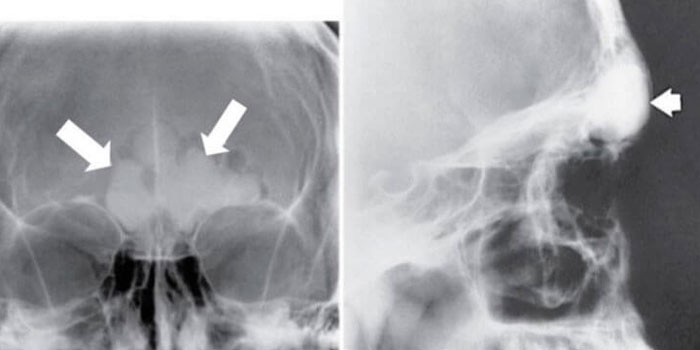

- Рентгенография (полуаксиальная проекция), УЗИ позволяют судить о форме пазух, наличии экссудата, отечности слизистой.